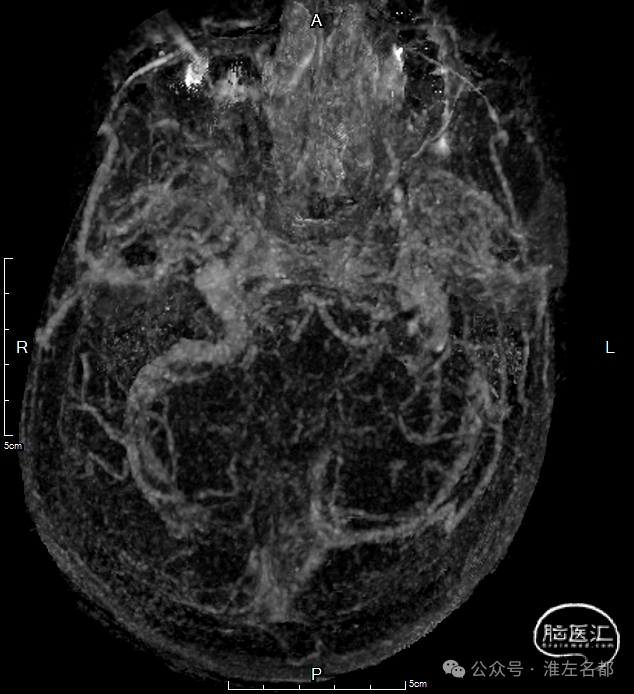

增强MRV:左侧横窦-乙状窦显影纤细;上矢状窦和右侧横窦-乙状窦充盈缺损;脑深部静脉和直窦未见显影。

SWI:双侧丘脑渗血改变,右侧基底静脉和大脑中静脉血栓。